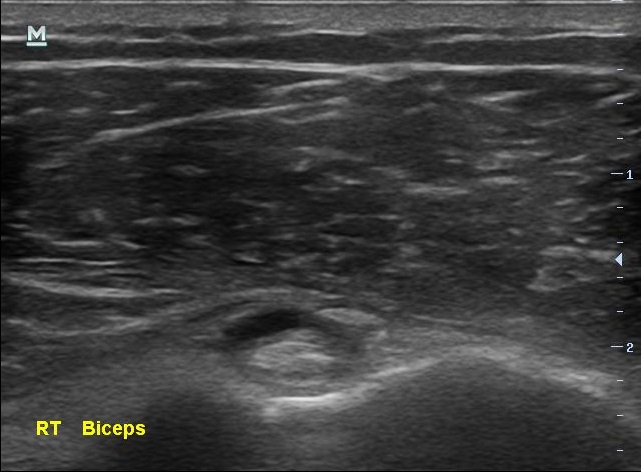

통증이 있지만 운동을 멈추지 않았다는 남자분.... 결과는 생각보다 나빴습니다. 초음파 검사상에서 이두박근의 장두에 염증이 보였고 극상근 힘줄에는 부분파열 소견이 보이고 있었습니다.

나 : 네... 이두박근 힘줄에는 염증이 있구요, 더 큰 문제는 극상근 힘줄에 부분 파열이 보인다는 겁니다. 현 상태만 놓고 보아서는 아직 수술까지 할 단계는 아니신데 앞으로 관리가 잘못되면 수술이 필요하실수도 있어요